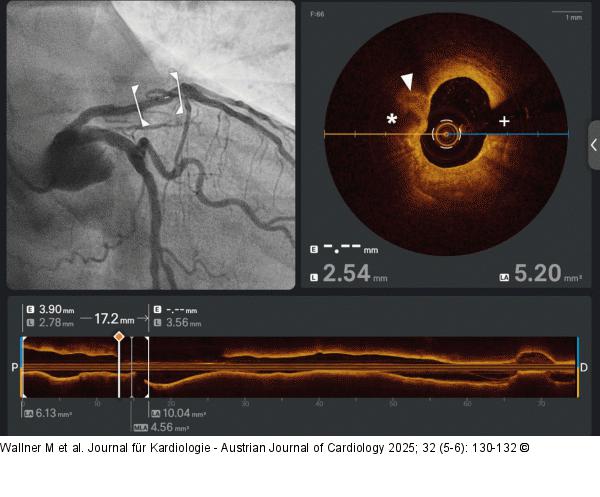

Abbildung 3: OCT OCT revealed a fibro-calcified plaque with lipid deposits (* = calcified areas, arrowhead = lipidic/fibrotic plaque, + = guidewire artefact) |

OCT revealed a fibro-calcified plaque with lipid deposits (* = calcified areas, arrowhead = lipidic/fibrotic plaque, + = guidewire artefact) |